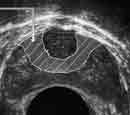

Эндовезикальное сканирование позволяет дифференцировать все слои мочевого пузыря (Рис. 1). Между мышечной стенкой и слизистой оболочкой визуализируется гипоэхогенная подслизистая соединительная ткань. При стадии рака мочевого пузыря Та (инвазия в пределах слизистой) создается впечатление, что опухоль отделена от мышечной стенки мочевого пузыря, то есть подслизистый слой остается неизмененным (Рис. 2), также хорошо визуализируются устья мочеточников. При распространении инвазии субэпителиальной соединительной ткани (стадия Т1) опухоль уже непосредственно прилежит к мышечному слою, но не инвазирует последний (Рис. 3).

Рис. 1. Цистэндосонограмма. Нормальная стенка мочевого пузыря.

1 - слизистая оболочка,

2 - подслизистая соединительная ткань,

3 - мышечная стенка.